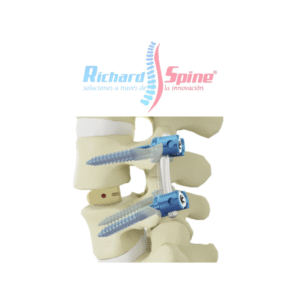

Placa de Fusión intercorporal cervical anterior

- La placa de fusión intercorporal cervical anterior es un dispositivo metálico utilizado en cirugía para estabilizar la columna cervical, específicamente en procedimientos de fusión intersomática anterior (ACIF). Esta placa se coloca en la parte frontal de las vértebras cervicales, después de la extirpación de un disco intervertebral dañado, para mantener la alineación y promover la fusión ósea entre las vértebras.